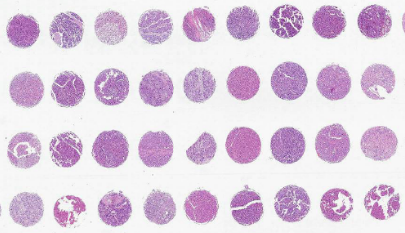

組織芯片制作步驟由普拉特澤生物病理實(shí)驗(yàn)平臺(tái)為大家分享,普拉特澤生物長(zhǎng)期為廣大科研人員提供組織芯片外包代做服務(wù)。組織芯片是繼基因芯片、蛋白質(zhì)芯片之后出現(xiàn)的又一種重要的生物芯片,主要用于研究同一種基因或蛋白質(zhì)分子在不同細(xì)胞或組織中表達(dá)的情況。

1、芯片微陳列設(shè)計(jì):在構(gòu)建組織芯片之前,應(yīng)該預(yù)先計(jì)劃?rùn)z測(cè)多少樣本,然后相應(yīng)地進(jìn)行設(shè)計(jì)。對(duì)大多數(shù)研究來(lái)說(shuō),在一個(gè)常規(guī)的載玻片上放置60~100個(gè)樣本已經(jīng)足夠了。當(dāng)樣本超過(guò)100例時(shí),上樣、切片、染色及研究各個(gè)步驟都要求相當(dāng)熟練,并且由于樣本排列過(guò)于緊密,有可能導(dǎo)致芯片制作和研究失敗。因此在計(jì)劃?rùn)z測(cè)數(shù)百個(gè)到上千標(biāo)本時(shí)可考慮多做幾個(gè)組織芯片。

3、TMA受體蠟塊制備:取97.5克萊卡石蠟+2.5克蜂蠟(2.5%)混合,制成長(zhǎng)36mm*寬26mm*高17mm的空白蠟塊,在該蠟塊20mm×16mm范圍內(nèi)設(shè)計(jì)10×8點(diǎn)組織陳列。組織四周預(yù)留0.5cm-0.7cm空間,用組織儀打孔制成TMA蠟塊。